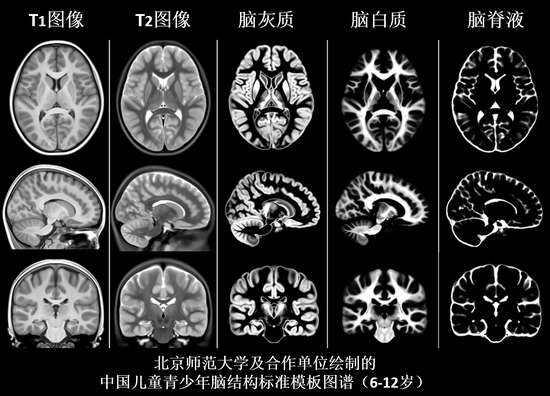

联盟团队初步揭示了儿童青少年发育过程的一系列变化规律,构建了精细年龄分段下的学龄儿童脑发育结构和功能图谱,脑灰质、白质和脑脊液概率图谱,以及以1岁为年龄间隔的各个精细年龄分段下的动态脑结构模板。这些工作是脑发育研究的基础。